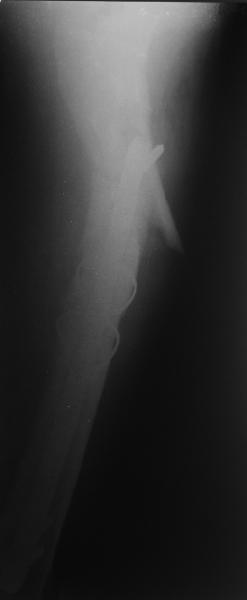

В общем, сделали. См. приложение.

Длина и из-за этого ось получились не совсем такие, как хотелось бы, все-таки срок после той операции уже 6 недель. Может быть, стоило провести дистракцию аппаратом неделю-другую. Заранее спасибо за комментарии и критику.